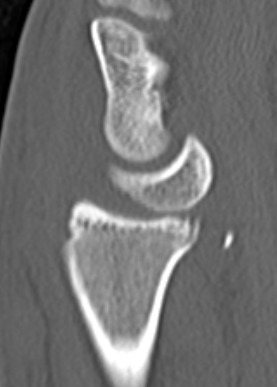

Lateral xray

Distal radius / lunate / capitate: not aligned, spilled teacup

Normal versus spilled tea cup appearance on lateral with spilled tea cup